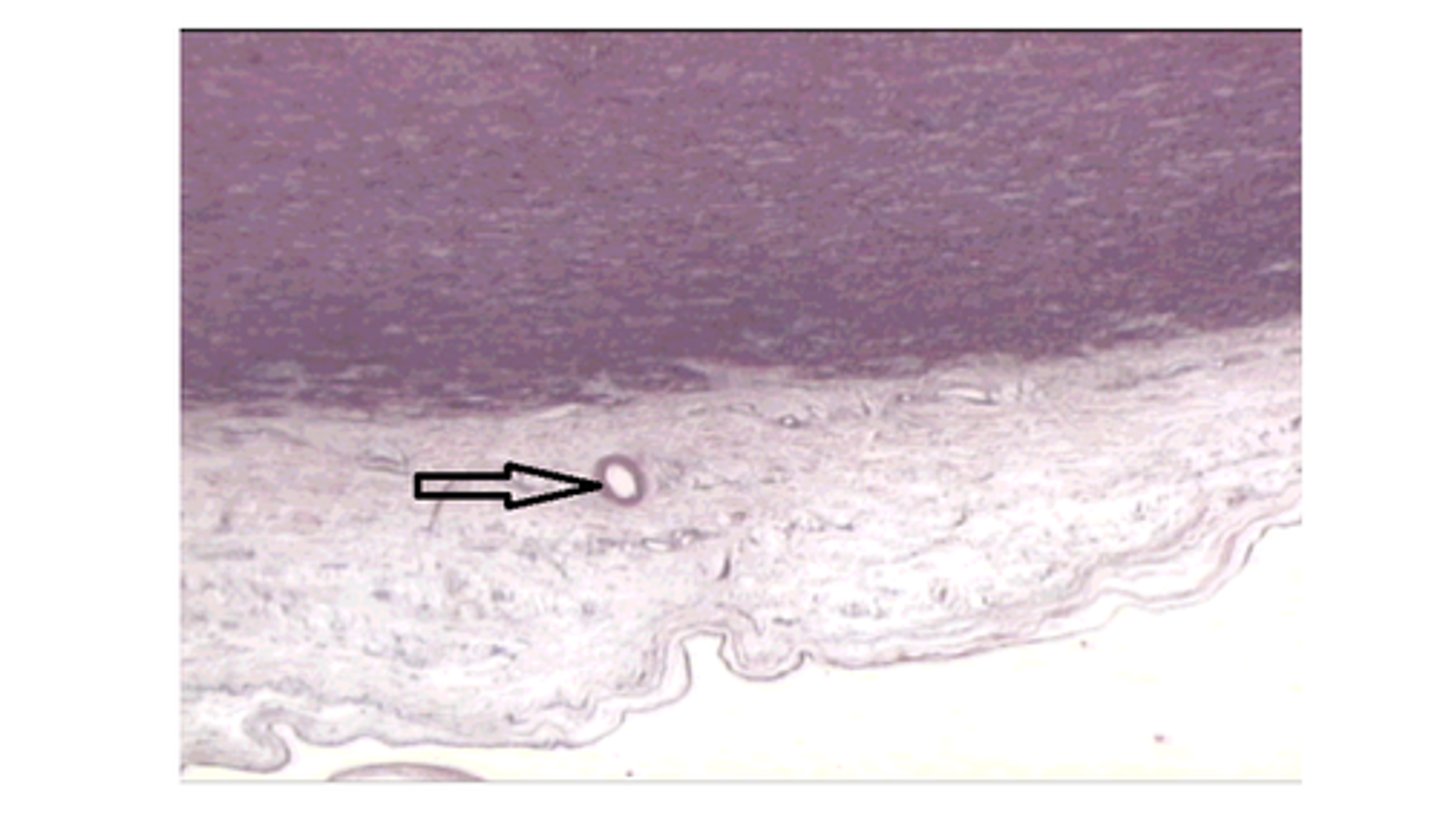

True

T/F: The arrow is at posterior segment of the eye which contains vitreous humor. inner chamber